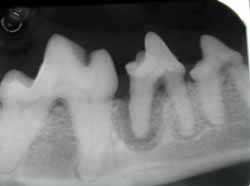

Questa infezione viene chiamata reazione periapicale ed è visibile radiograficamente.

La pulpite può determinarsi anche a seguito di un processo carioso che si approfondisce nella dentina oppure in seguito alla progressione della malattia parodontale che distruggendo l’osso alveolare può arrivare ad infettare la polpa progredendo attraverso il legamento parodontale.

Lesione cariosa che si approfondisce nella polpa dentale